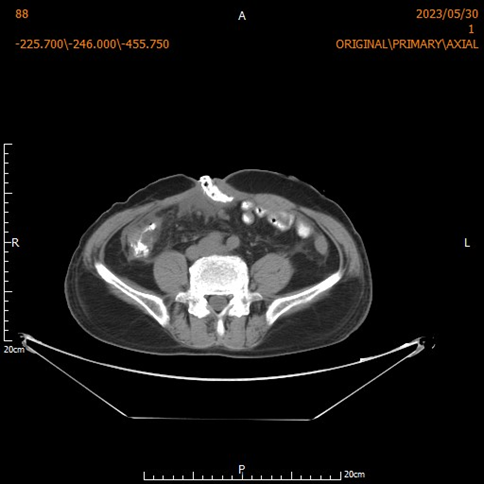

生死72小时!广西民族医院多学科协作成功抢救一例盆腹腔脓肿脓毒症...本文转自:人民网-广西频道近期,广西民族医院成功救治一名因盆腹腔脓肿导致脓毒血症休克的危重患者。该患者因腹痛拖延就诊,病情急转直下,入院时已出现感染性休克和多器官功能衰竭倾向。医院紧急启动多学科会诊,仅用3小时完成诊断与决策,并在6小时手术中彻底清除超过2000毫...